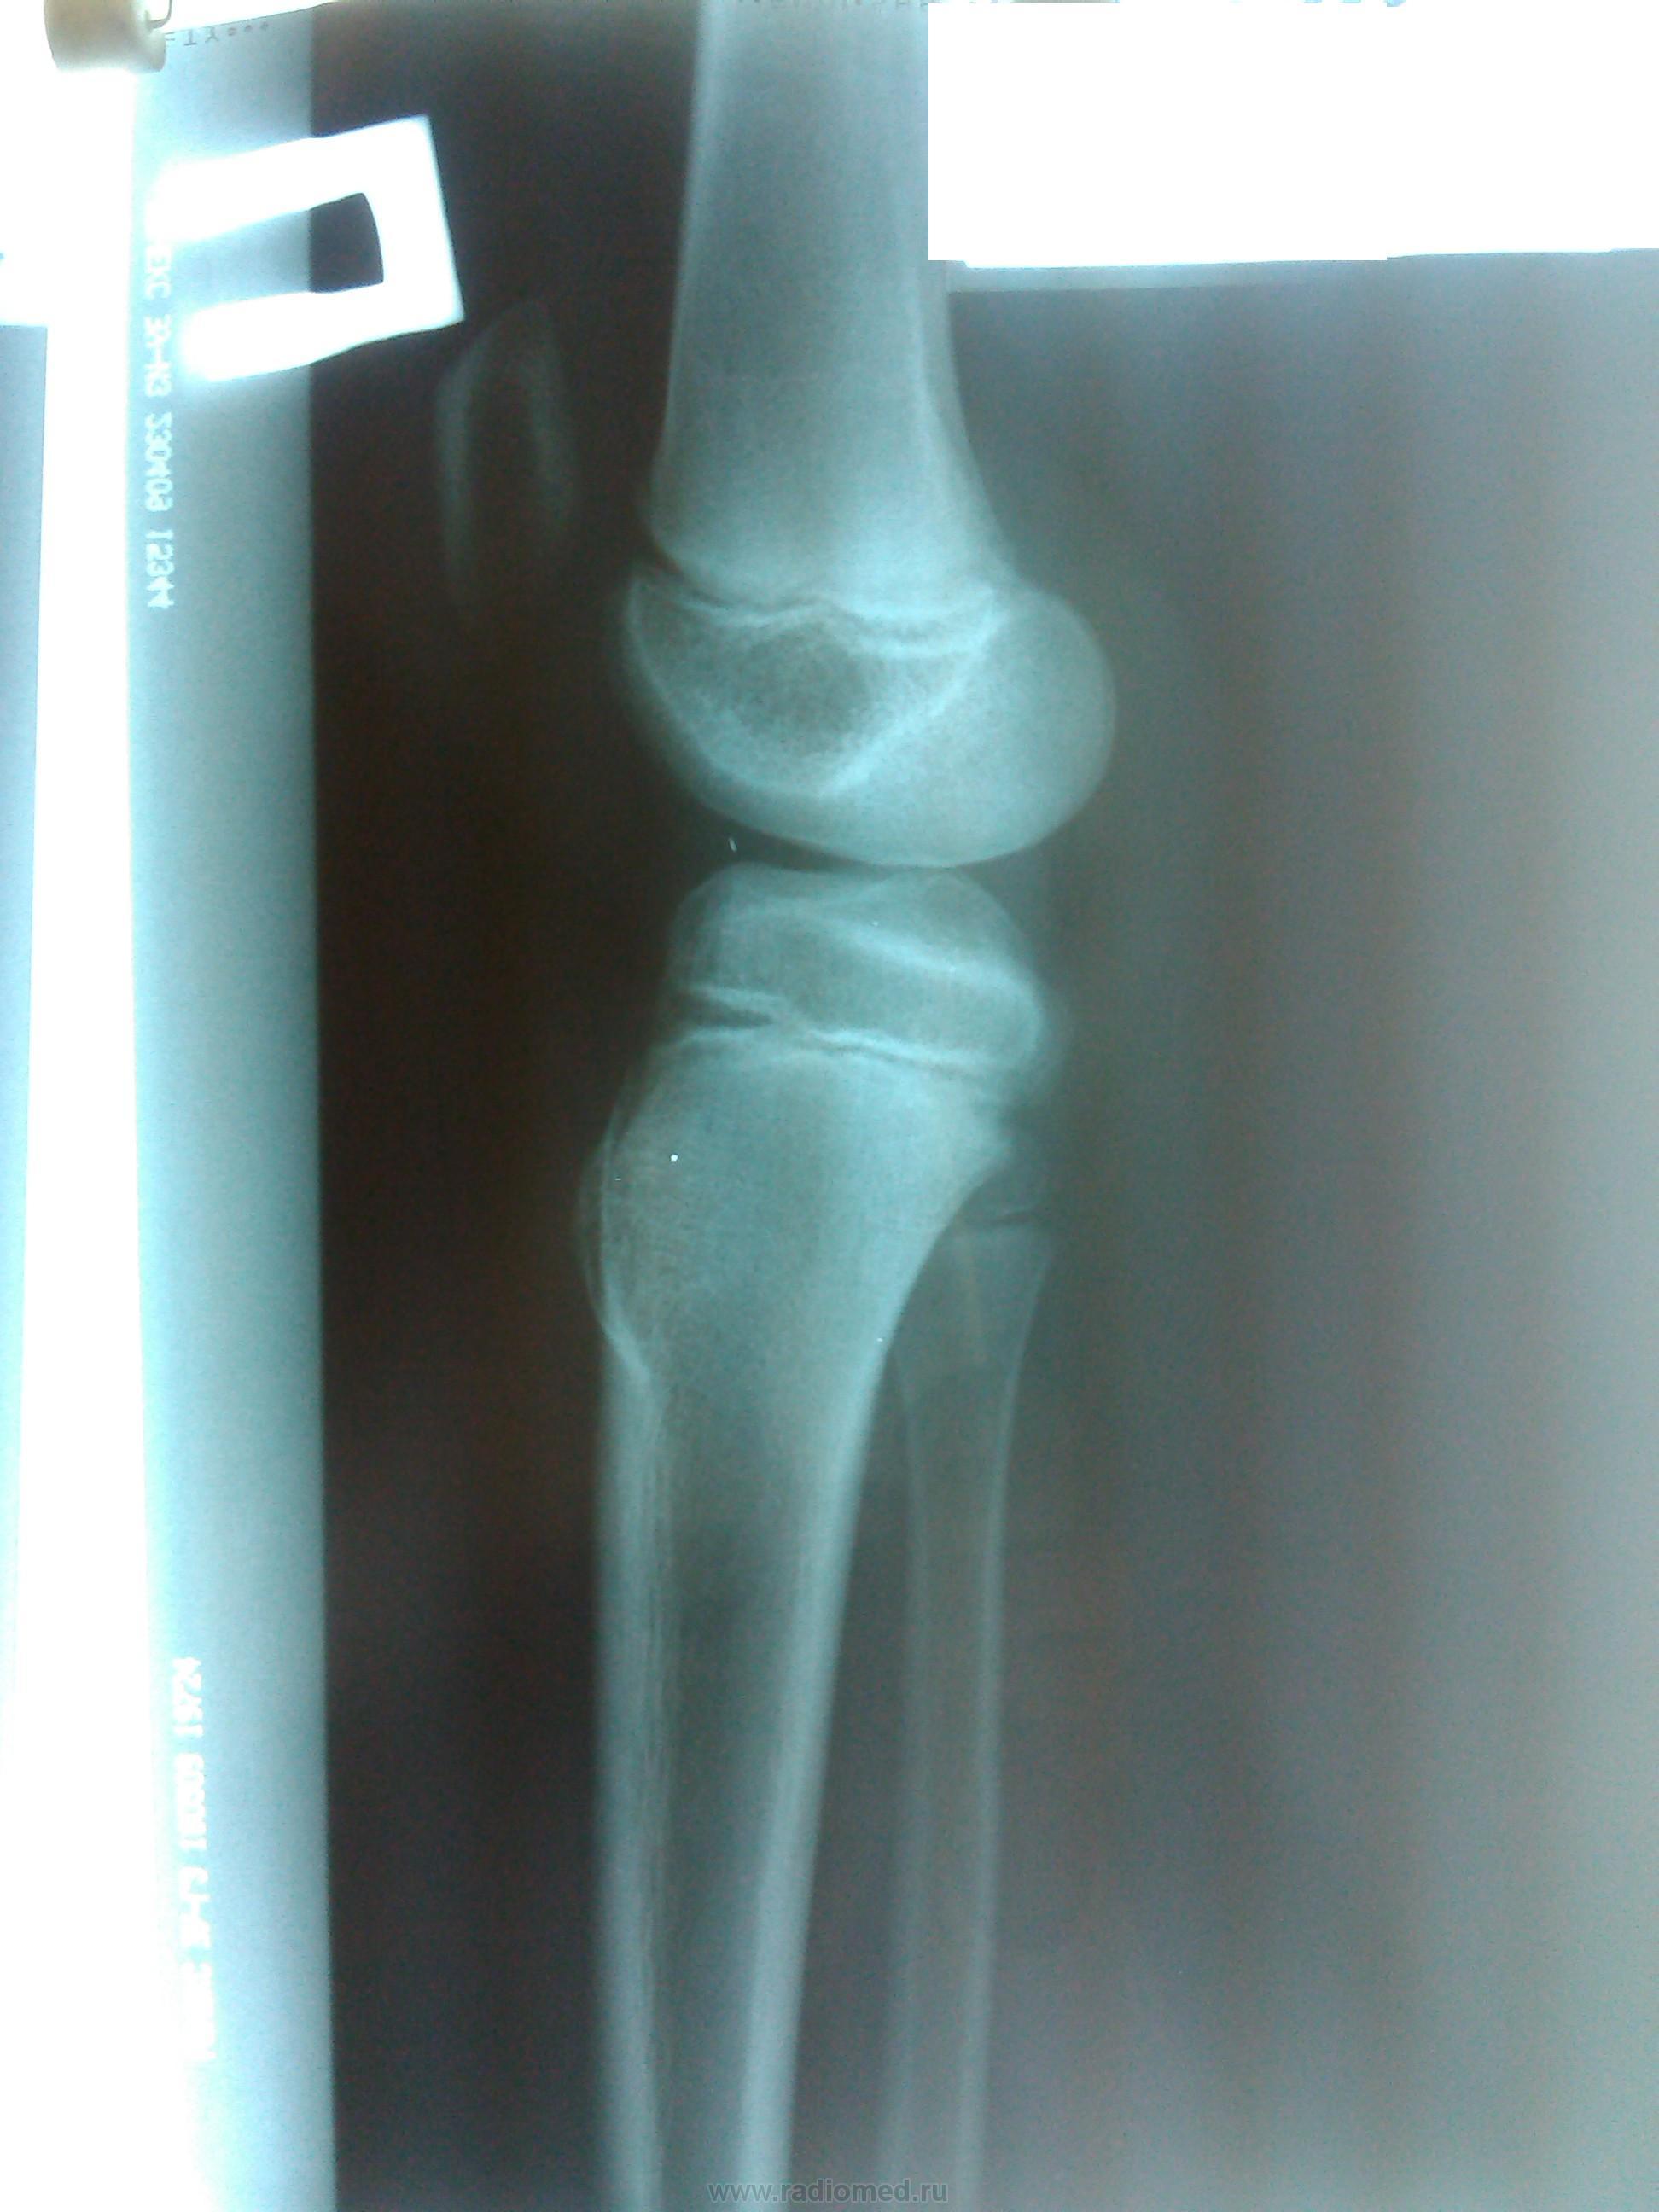

Пациент, 8 лет. Остеохондрома или остеома?

Почему сразу о саркоме? Периостальной реакции нет, лизиса тоже... Признаков злокачественного роста нет.

Локализация самая "экзостозная", но, учитывая широкое основание, можно думать и об остеоме.

Холмовидный костно-хрящевой экзостоз.

Ну а клинически? Потому, что скорее находка, чем болезнь, по структуре - обычный экзостоз.

Все же как -то не спокойно по поводу остеогенной саркомы. Даже при отсутствии клиники написал бы рентгенконтроль через 2 недели.

В 8 лет надо быть на стороже  + за  контроль в динамике

широкобазальный костно-хрящевой экзостоз.не остеома(локализация не та и структура иная)